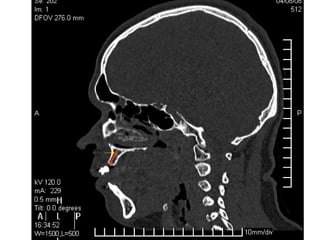

Tomografía computarizada

De seno maxilar corte sagital.

Area de implantación

Dentaria.

Material osteoconductor

para elevar el piso antral

Nuevo piso del seno y su

margen de seguridad para

contener el implante

Tomografía computarizada De senomaxilar corte sagital. Area de implantación Dentaria.

Nuevo piso delseno y su margen de seguridad para contener el implante dentario